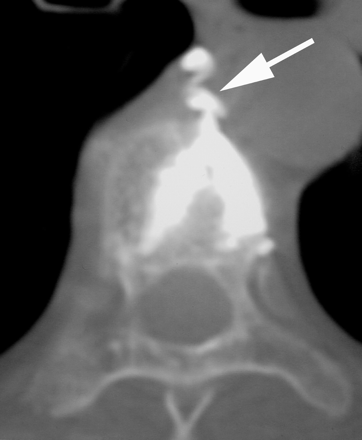

CT scan of a thoracic vertebra following KP. There was a lateral blowout fracture of the vertebra caused by balloon inflation and a large cement leak (arrow) into the mediastinum. The patient had severe pain requiring hospitalization and protracted analgesic therapy for weeks following therapy. (From JM Mathis. Percutaneous vertebroplasty. AJNR Am J Neuroradiol 2003; 24:1697–1706; by permission.)